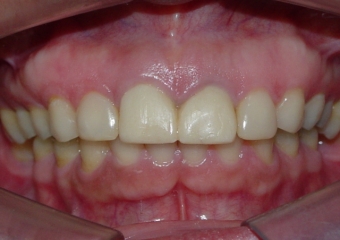

Sorriso final, do caso terminado em outubro de 2011

Sorriso Final, Controle em 2013